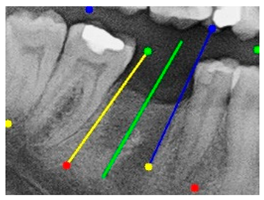

| Comparison with dentist’s ground truth (black line) and our framework (green line) | ||||||

| Validation Image 1–6 | ![]() | ![]() | ![]() | ![]() | ![]() | ![]() |

| MSE | 3.59 | 1.29 | 0.41 | 0.80 | ||